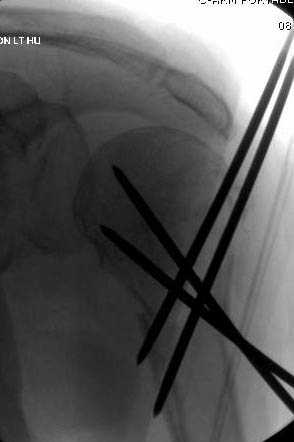

Наш недавний случай перкутанной фиксации "методом

Сиэтла" спицами 2.8 мм с резьбой на конце.

Имя     : 3 Proximal humerus CRM.jpg

Url     : http://weborto.net:8080/pipermail/ortho/attachments/20071128/ffd31465/attachment-0007.jpg